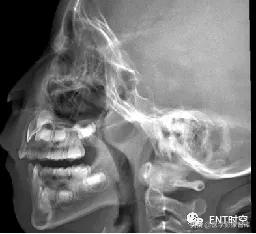

四、 鼻咽部侧位X片的摄片方法

患儿端坐或站立侧位,下颌略抬高,以减少下颌支与鼻咽腔重叠,眶耳线平行于地面,头颅矢状面与摄片架平行,中心线通过外耳孔前下方约2cm处,嘱患儿闭口用鼻吸气并摄片,防止软腭抬高造成鼻咽腔变窄的假象。